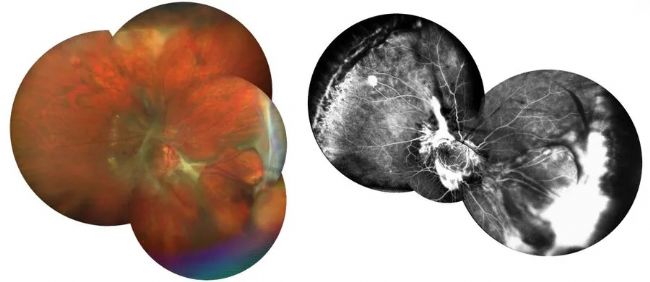

一名患有馮-希佩爾-林道(VHL)綜合征的 30 歲女性失去了左眼,右眼視力仍相對較好,但視力正在下降。她的左眼失明,右眼視力仍相對較好,但視力卻在下降。她的右眼有大量眼膜需要切除,還有幾個血管母細胞瘤,其中一個非常大(圖 9)。

圖 9:術前圖像。患者有多個血管母細胞瘤,其中一個非常大。圖片由 Nikolaos Bechrakis 教授提供。

術中 OCT 顯示視網膜脫落,而且術前沒有看到的是視網膜下膜和視網膜下間隙的血管瘤(圖 10)。這對了解具體情況以及牽引性視網膜脫離是如何形成的非常有用。通過評估,外科醫生得出結論,牽引性視網膜脫離不僅是由視網膜外膜造成的,也是由視網膜下膜造成的。

圖 10:術中 OCT 圖像顯示,視網膜下有一層膜,視網膜下間隙有一個血管瘤。圖片由 Nikolaos Bechrakis 教授提供。